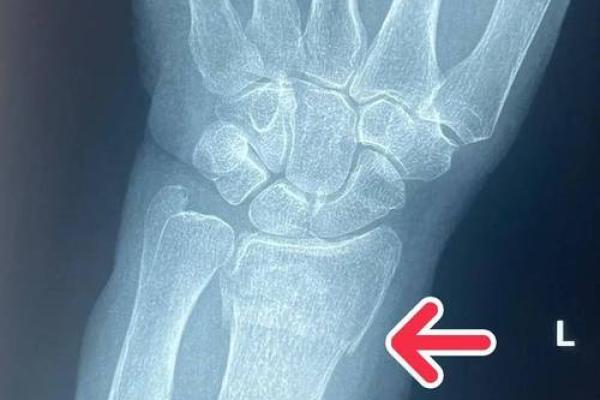

首先,桡骨和尺骨在解剖学上的定位极为重要,桡骨位于前臂的外侧,而尺骨则位于内侧。桡骨的直接影响在于它的强大支撑作用,使得手腕在活动时能够保持灵活。而尺骨则负责承载部分力量,二者的配合使得我们的手腕可以自由转动,完成诸多精细的动作。这种结构上的搭配并非偶然,而是自然界对生物结构最优化的一种体现。

在医学上,桡骨和尺骨的健康同样是我们日常生活中的重要一环。许多人在进行运动或劳作时,不注意保护手腕,导致了桡骨或尺骨的损伤。这不仅会影响活动的能力,还可能对整个生活造成负面影响。因此,保持手腕的健康,了解这些骨头的运行机制,对于我们来说显得尤为重要。在日常生活中,应当注意手腕的保暖和保护,适当的锻炼以增强手腕的力量与灵活性。